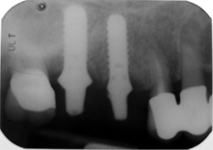

Při ztrátě molárů a premolárů v horní čelisti a jejich náhradě implantáty se často setkáváme s nedostatečnou

vertikální nabídkou kosti pod čelistní dutinou, často doprovázenou i nedostatečnou horizontální nabídkou a sníženou kvalitou kosti (v oblasti 2. premoláru v 50%, v oblasti moláru až v 80% případů nedostatečná kostní nabídka)

Od roku 1985 je tento problém řešen augmentační operací nazývanou

sinus lift.

Jedná se o vyzvednutí membrány, která čelistní dutinu vystýlá, pod vyzvednutou membránou vznikne kapsa, kam se umístí augmentační materiál, do kterého se zavedou implantáty.

Vhojení implantátů se při této operaci prodlužuje na 6-12 měsíců.